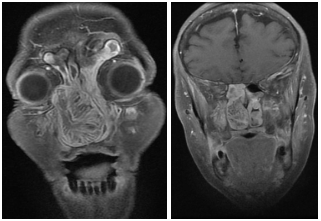

El diagnóstico diferencial de papiloma invertido y otras masas de la fosa nasal es de difícil determinación, siendo necesaria las mediciones densitométricas tomográficas. Los valores densitométricos de la masa en las adquisiciones en nuestro paciente sin contraste se encuentran entre 55 - 60 UH y posterior a la infusión del contraste oscila entre 70 - 80 UH; el cornete medio presenta densidades entre 40 - 45 UH, mientras que las secreciones mucosas muestran valores entre 25 - 40 UH. Si bien estos realces no son específicos para realizar el diagnóstico de papiloma invertido, podrían ser de utilidad para la valoración de la extensión del mismo (Figura 1 – 2).

En RM, secuencia en T1, la lesión se observa hipo-isointensa y se proyecta desde orificio nasal hasta Cavum y coana, con aspecto de lesión solida expansiva ubicada sobre seno maxilar derecho que se extiende alrededor de la pared interna del seno nasal hacia la fosa nasal homolateral y se proyecta hasta senos frontales y presenta erosión de la lámina papirácea (Figura 5 – 6 – 7).

En secuencia T2 sin contraste, la lesión presenta áreas hiperintensas y de baja señal, determinando marcado desplazamiento del tabique nasal y oblitera trompa de Eustaquio derecha, con ocupación de celdillas mastoideas y oído medio homolaterales (Figura 8–9-10).

En RM con contraste la lesión presenta un realce intenso al gadolinio (Figura 11 – 12 – 13).